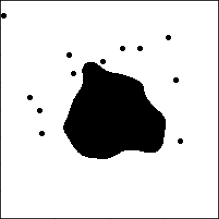

3 Simulation Study

We conduct simulation studies under two scenarios. For each scenario, we randomly generate 100 binary tumor images of size pixels from two groups of A and B, respectively, and create 30 independent datasets. In scenario 1, the main tumor region is created by applying Gaussian smoothing and thresholding to 50 points sampled from the bivariate normal distribution. Then, up to 5 and 20 random points are added as small tumor regions to groups A and B, respectively. The two groups mainly differ by the number of small disconnected tumor regions, summarized in quadrant IV of the dimension-zero persistence diagram, as illustrated in Figure 2(a). In scenario 2, larger main tumor regions are created similar to scenario 1, and up to 20 small tumor regions are added to both groups. For group B, up to 50 holes are created around the boundary of the main tumor region. The tumor region with holes corresponds to topological features in quadrant III of the dimension-zero persistence diagram, as shown in Figure 2(a). The simulated tumor image examples of two groups are given in the left panels in Figures 4(a) and 4(b).

We transform the simulated images by the SEDT for two-class (SEDT-2). The SEDT-2 is a simpler version of the SEDT-3; it does not assign infinite values because the generated images do not have empty regions. Interpretation of the topological shape features of binary images is similar to interpretation of the three-class images shown in Figure 2, except that there are no topological features that summarize separate non-tumor regions (e.g., E and F in Figure 2(a)).

Persistent homology is computed as illustrated in Section 2, and the results are represented as persistence surface functions using smoothing parameters . We replace the dimension-zero persistence result with infinite death value with .

The functional coefficients of the proposed model show which shape patterns contribute the most to hazard. The average estimated dimension-zero functional coefficients are shown in the right panels in Figures 4(a) and 4(b). The coefficients show how topological features are associated with the survival prognosis; the blue-colored and red-colored areas are positively and negatively related to the hazard function, respectively. Thus, if a larger number of topological features appear in the blue (red) region, it is associated with higher (lower) hazard. For scenario 1, the topological features summarized in quadrant IV of the dimension-zero persistence diagram in Figure 4(a) are positively associated with hazard. This is consistent with group B having a larger number of small disconnected tumors than group A. Also, for scenario 2, the topological features that appear in quadrant III near the origin of the dimension-zero persistence diagram in Figure 4(b) are related to higher hazard. This corresponds to the tumor regions created by small holes. The red-colored region around in Figure 4(b) shows the difference of the size of tumor regions. Because the holes are added to the main tumor region in group B, its size, measured by the radius of the largest circle that can be placed inside, is smaller than that of group A. The coefficient of dimension-one functional predictors is not reported because they are not selected for more than half of the datasets.